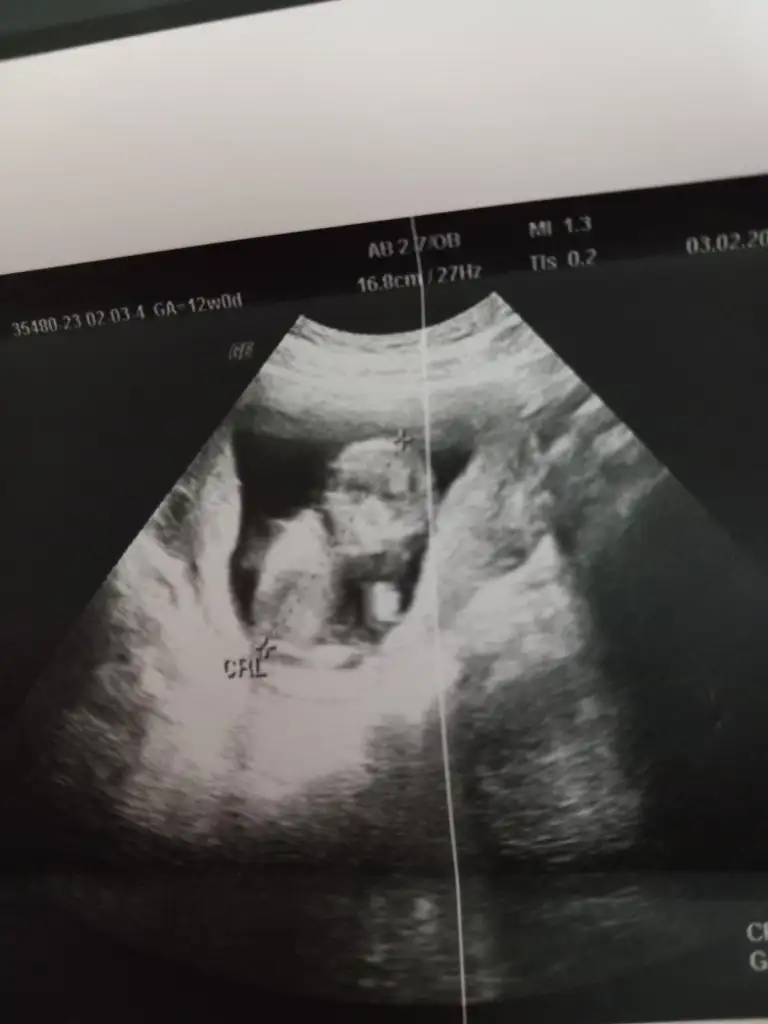

Banada bakar mısınız lütfenn 12 haftalik tamKarından ultrasonsa erkek vajinelse kız

6-9 haftalık fotosunu atarsanız yaparım burda bebişiniz çok büyük böyle bilemiyorum maalesefBanada bakar mısınız lütfenn 12 haftalik tam

Karından ultrasonmuEki Görüntüle 3202132 bana'da bakarmisiniz 9 haftalık

Doktorum erkek diye bunu elime tutuşturdu ama bi şey anlamadım hiç

Hayır vajinal ultrasonKarından ultrasonmu

6-9 haftalık fotosunu atarsanız yaparım burda bebişiniz çok büyük böyle bilemiyorum maalesef burda 7 hafta 5 günlük

Her türlüsü mevcut fotoların da işte ben de ah bi anlasamHeh işte böyle fotolar lazım banaKız gibi geldi canım bana karından ultrasonsa eğer